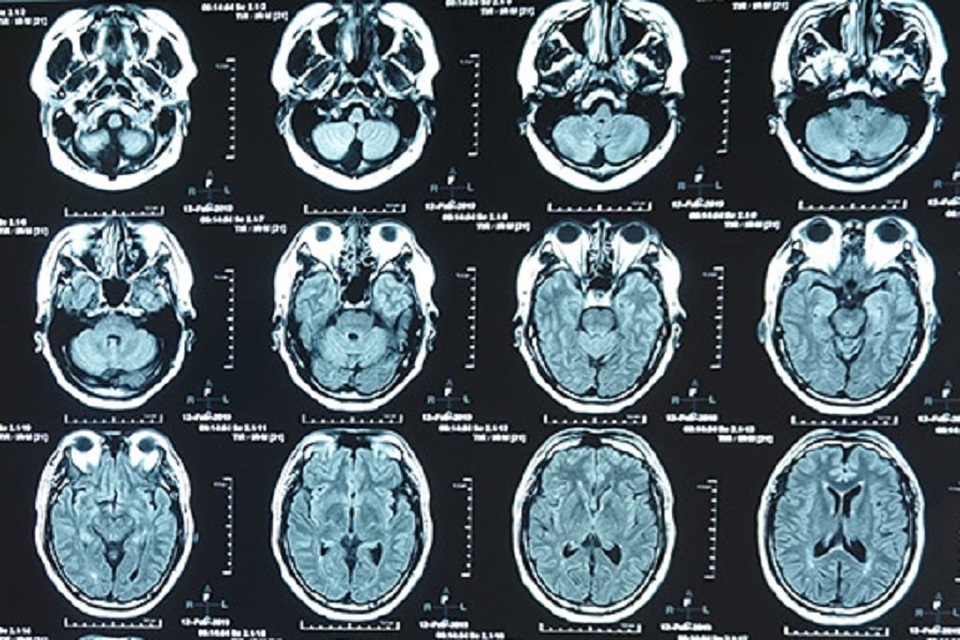

Bệnh nhân nhập viện ở giờ thứ 5 sau khi bị nhồi máu não cấp

Qua thăm khám, kiểm tra hình ảnh, bác sĩ chẩn đoán người bệnh bị nhồi máu não cấp giờ thứ 5. Sau cuộc hội chẩn nhanh giữa các liên chuyên khoa, bệnh viện đã quyết định cho bệnh nhân sử dụng thuốc tiêu sợi huyết qua đường tĩnh mạch. Khoảng 1 giờ sau khi tiêm thuốc, sức khỏe bệnh nhân nhanh chóng được cải thiện, chân tay có thể cử động, đi lại gần như bình thường.

Việc chỉ định sử dụng thuốc tiêu sợi huyết kịp thời đã giúp bệnh nhân nhanh chóng bình phục